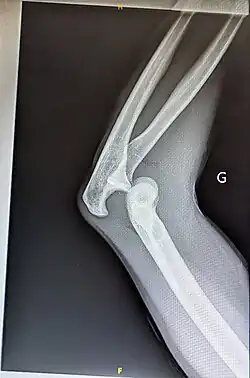

Displaced humerus fracture

Reduction is a medical procedure to restore the correct anatomical alignment of a fracture or dislocation. When an injury results in a fracture, or broken bone, the bone segments can sometimes become misaligned. This is referred to as a displaced fracture, which requires the medical procedure called reduction.[1] Some providers may refer to this as 'setting the bone'. When an injury results in a dislocation of a joint, or the misalignment of two connecting bones,[2] a similar process of reduction must be performed to relocate the joint back into normal anatomical positioning. In the case of both displaced fractures and joint dislocation reduction is required for effective healing.

There are two main categories of fracture reductions: closed reductions and open reductions. Both procedures require confirmatory imaging – such as X-ray – both before the reduction to confirm the misalignment of bones and after the reduction procedure to confirm successful achievement of anatomical positioning.